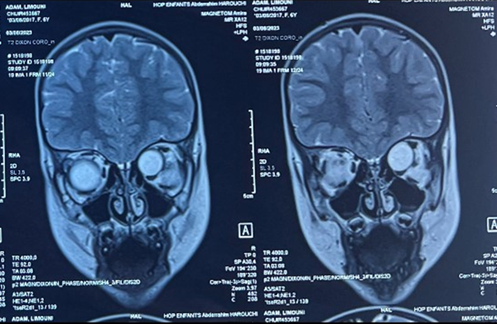

The orbital mri showed an oval,

well-limited left intra-orbital process, with regular contours and

extra-conical development, in hypo-signal in t1-weighted images, and in

homogenous hyper-signal in t2 weighted images, not enhanced after gadolinium

injection, and measuring 31 x 17 mm extended over 17mm, evoking a neuro-fibroma

or a schwannoma (figure 3).

Figure 3. T2-weighted coronal images of the orbital mri scan showing the hyperintense mass located in the superior and medial part of the left orbit